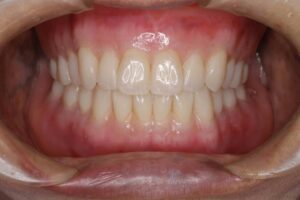

治療後 最初に治療用義歯を装着することにより、傷ついた土台の粘膜の改善と噛み合わせの正常化を図られたことから、最終義歯としてBPS義歯を装着しました。義歯の吸着は良好で、患者さんの生活の質(QOL)は向上し、大変満足いただけました。

治療用義歯の装着により「よく噛めるようになった」とのお話が聞け、入れ歯の土台となるあごの粘膜が健康になって、下顎左側偏位の修正が得られました。そこで最終義歯(BPS金属床義歯)を製作していくこととしました.製作ステップは治療用義歯製作と変わりません。見た目を綺麗にしたいとのご要望があり、歯肉の相当する部分をカラーリングして、より自然感のある美しい義歯に仕上げました。患者さんの笑顔も見られ、初診時に障害されていた生活の質(QOL)も70満点中14点と全ての項目で向上して、ご満足が得られました。